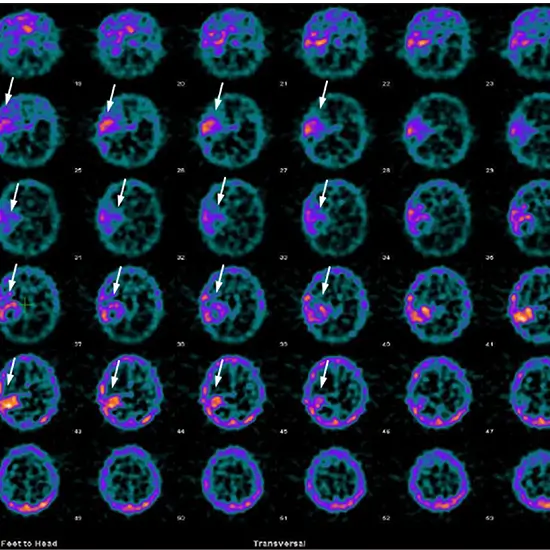

A test that looks for changes in brain blood flow patterns is called MIBI Brain Single-photon emission computed tomography (MIBI Brain SPECT). It is used to evaluate brain tumors and is highly recommended for visualizing high-grade tumors. Blood flow in the area of the brain where seizures begin is at its peak during a seizure.

• To indicate areas of increased brain activity due to increased blood flow to these areas in epileptic patients who have undergone other tests like EEG or MRI but the location of origin of the seizures could not be determined.

• This is used to visualize and evaluate brain tumors